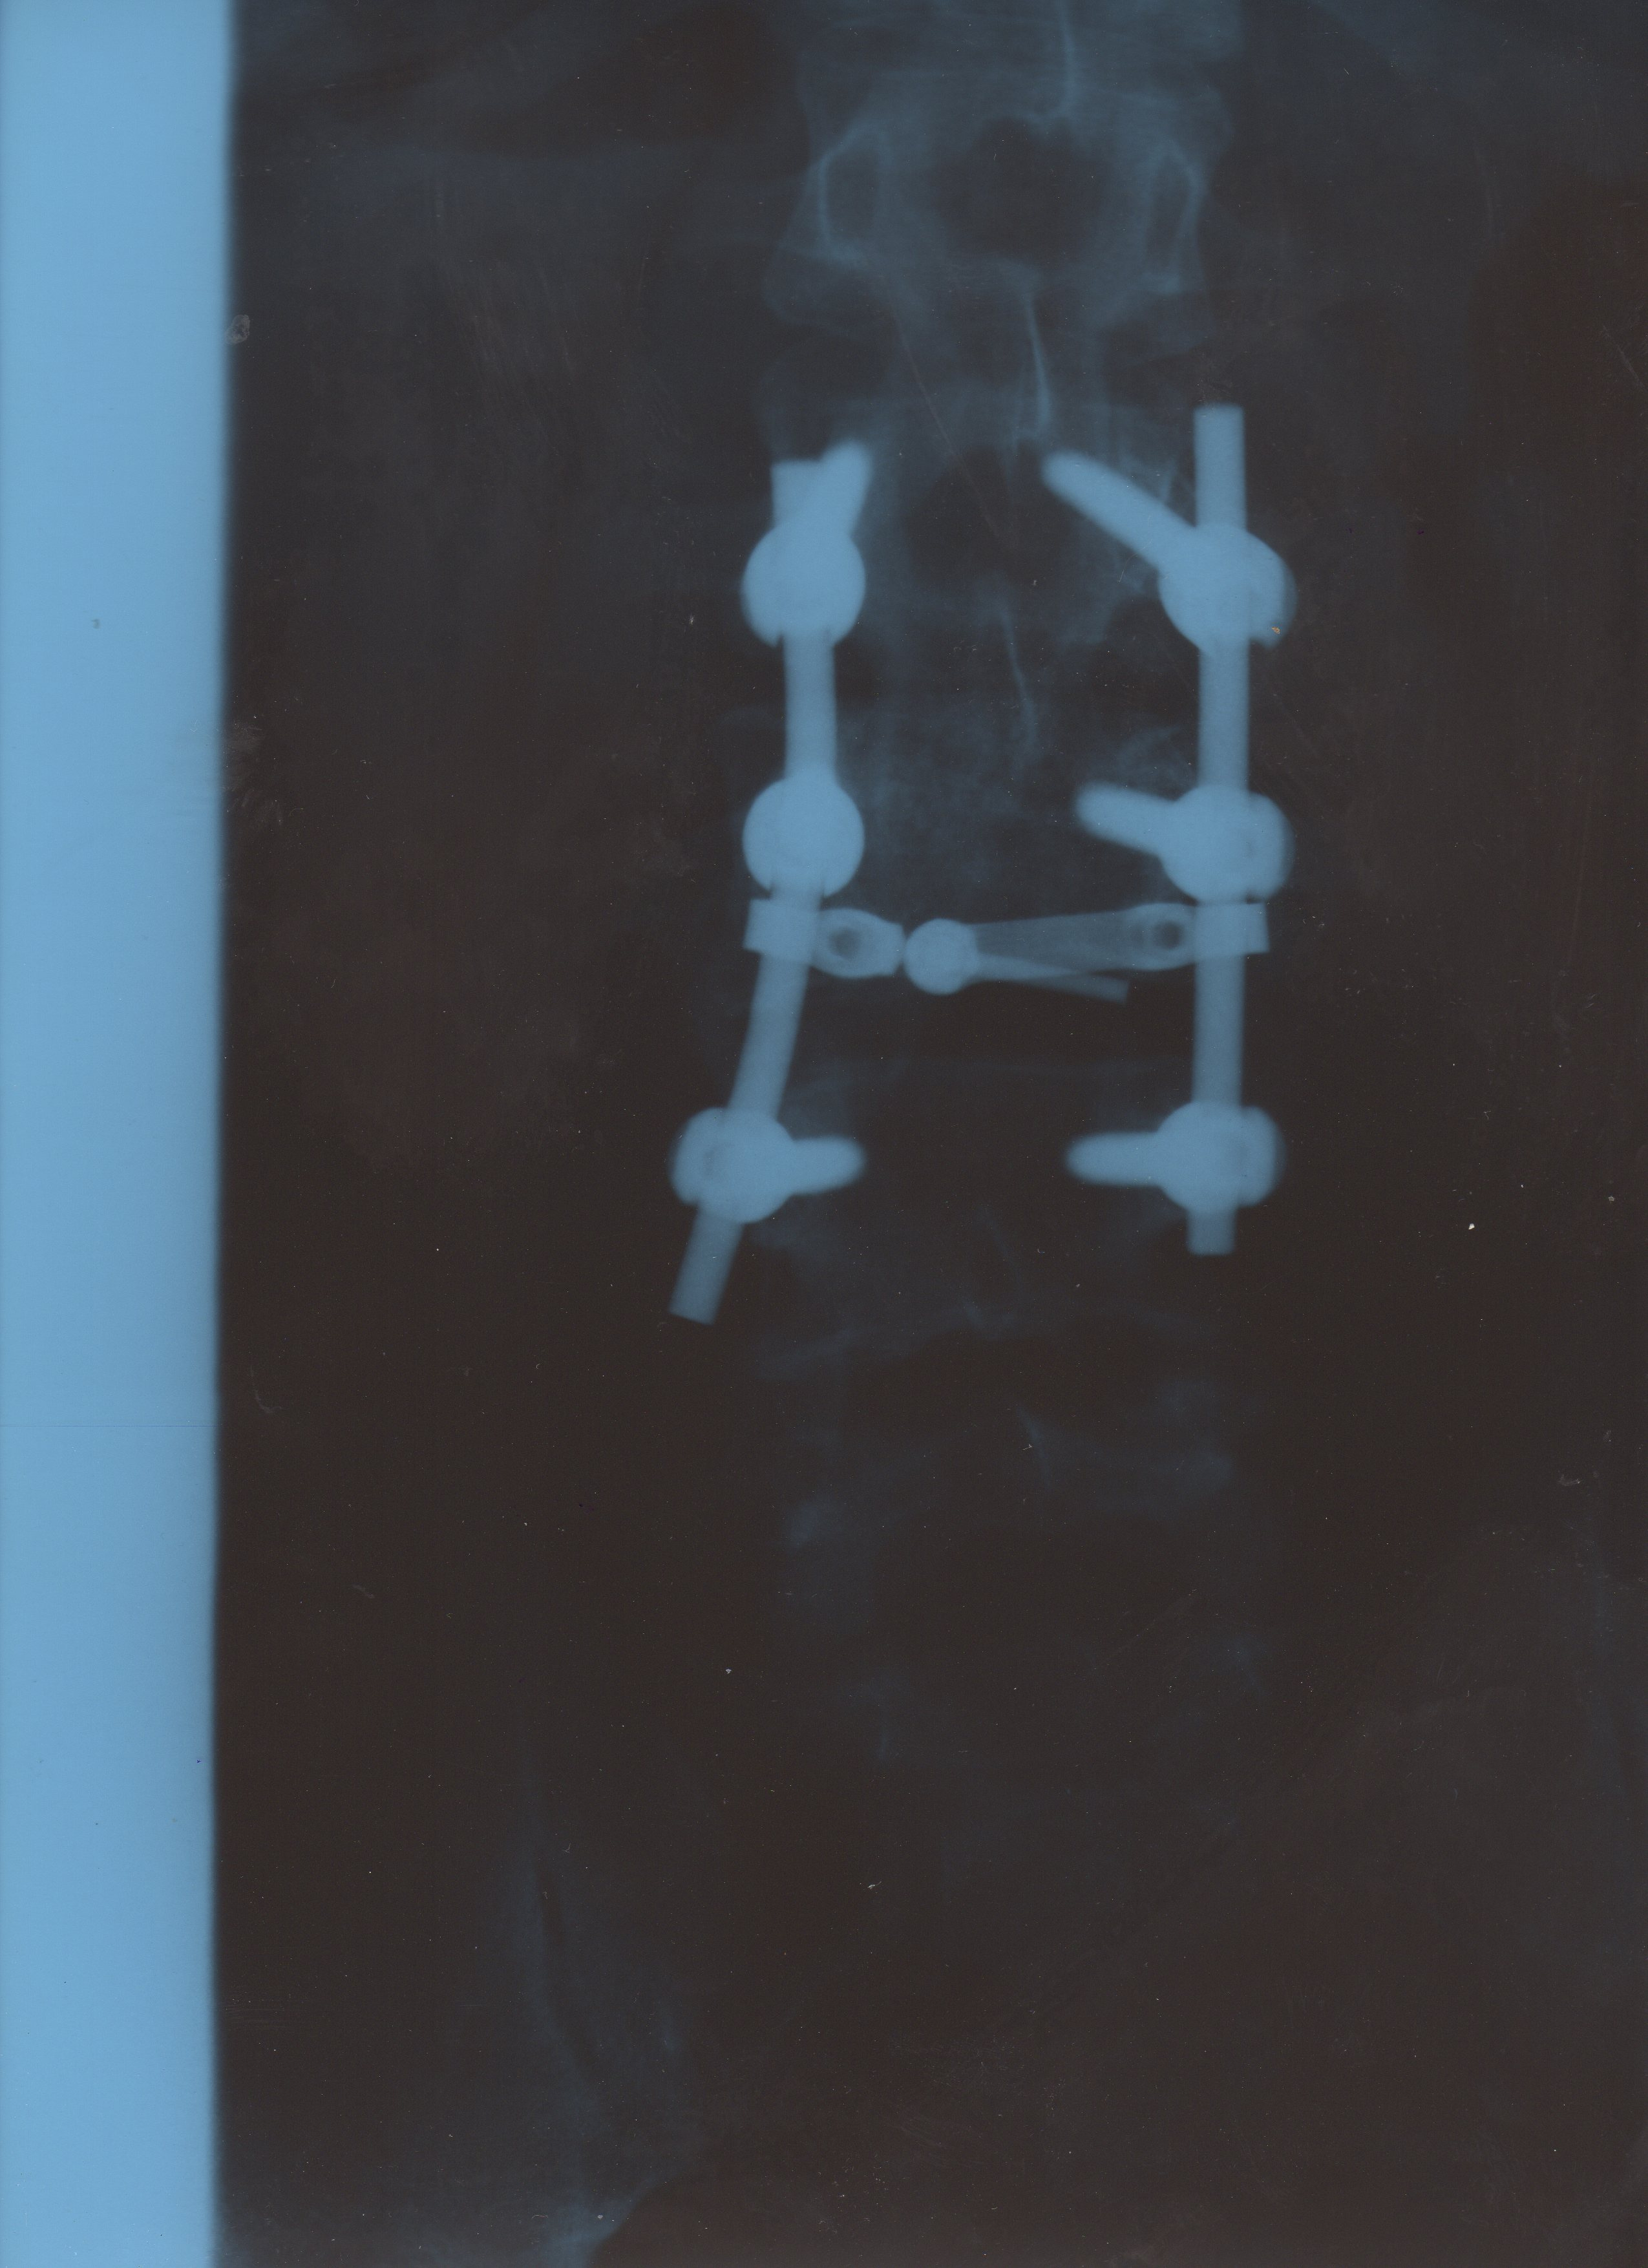

About 20 years before I served at Elk Neck State Park, in my naïveté I was involved in an accident involving snow, ice, inertia, and unfortunately gravity - which resulted in three fused vertebrae. The surgeon said I was 2 centimeters away from being paralyzed from the waist down.